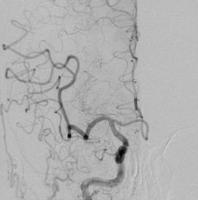

血栓回収療法

術前

術後

脳の血管に血栓が詰まって血流が途絶えると、脳細胞は急速に壊死していき脳梗塞を起こします。

脳梗塞による重篤な後遺症をできるだけ回避できるよう、可能な限り早く詰まった血栓を取り除いて血流を再開させ、脳へのダメージを最小に抑えることを目的に行う治療です。

閉塞血管までカテーテルを進め、器具を用いて血栓を掻き出したり吸い出したりして取り除きます。